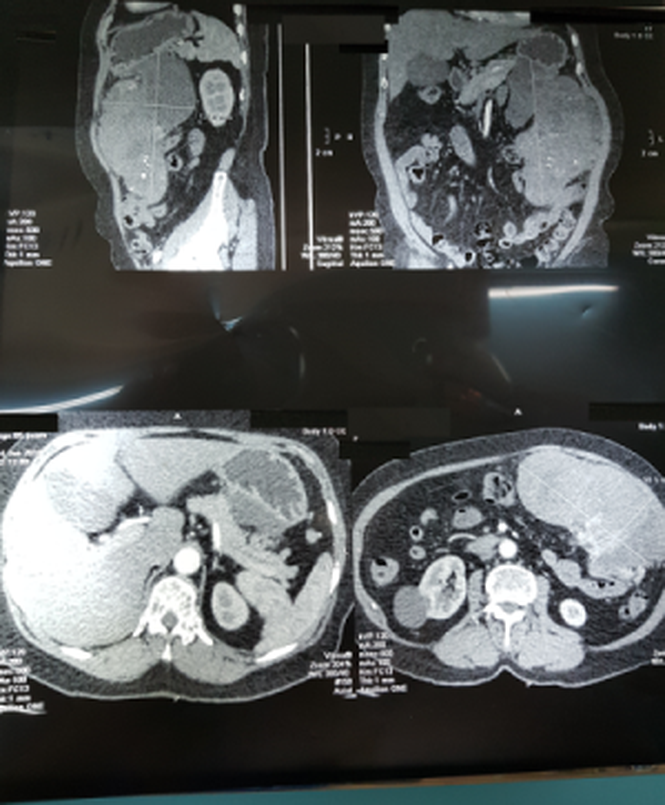

Ngay ở bước thăm khám lâm sàng, các bác sĩ tại trung tâm đã ghi nhận một khối u lớn, ấn không đau, khu trú ở vùng hạ sườn trái. Kết quả siêu âm cũng cho thấy một khối u kích thước lớn, chưa rõ bản chất. Bên cạnh đó, kết quả CT scan khảo sát vùng bụng phát hiện khối u mô đệm thành dạ dày, choán chỗ toàn bộ vùng hạ sườn trái, có đường kính lớn nhất lên tới 20 cm.

Bác sỹ toát mồ hôi cứu người phụ nữ suýt chết vì khối u khủng ảnh 1

Kết quả CT scan khảo sát vùng bụng phát hiện khối u mô đệm thành dạ dày